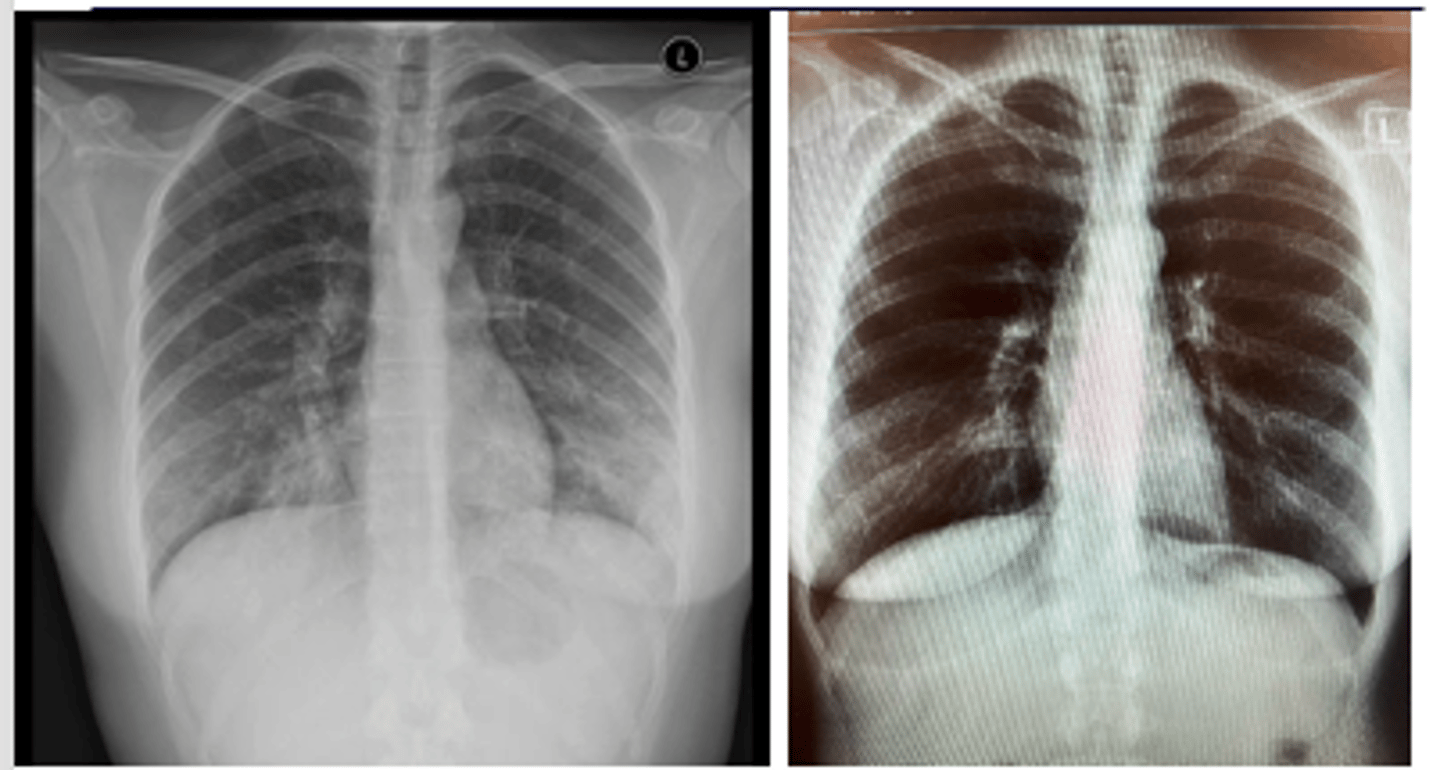

ID picture on back

LLL pneumonia

<p>LLL pneumonia</p>

RUL pneumonia with air bronchogram sign

<p>RUL pneumonia with air bronchogram sign</p>